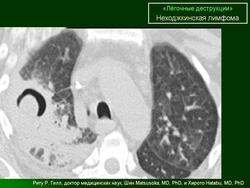

ОГК. Легочные деструкции (кавитации). +

Легочные деструкции (кавитации)

Легочные кавитации. Радиопедия.